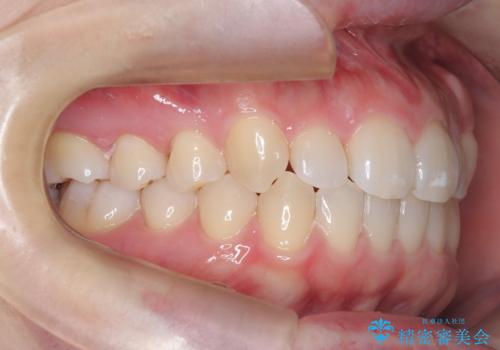

- 患者様は歯並びの乱れを気にされて来院されました。特に小臼歯の捻転(ねじれ)が強く、見た目だけでなく噛み合わせにも影響がありました。できるだけ目立たない方法を希望されていたため、インビザライン(マウスピース矯正)を基本としつつ、より精密な動きが必要な部分にはワイヤー矯正を併用する計画を立てました。また、小臼歯の捻転については**部分矯正(MTM:Minor Tooth Movement)**を取り入れ、効率的に改善を目指しました。

まず、全体の歯並びを整えるためにインビザラインを使用し、徐々に理想的な位置へと歯を移動させました。一方で、ねじれの強い小臼歯に対しては、**部分的なワイヤー矯正(MTM)**を行い、より精密なコントロールを実施。約2年の治療期間を経て、歯並びと噛み合わせが整い、見た目の美しさだけでなく、機能的な改善も達成しました。患者様からは「自然な仕上がりで、自信を持って笑えるようになった」と喜びの声をいただきました。